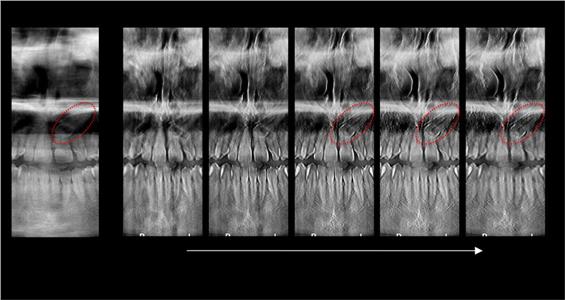

За само 13 секунди се добива високо квалитетна ортопантомграфска снимка, странична смнимка, снимка на вилични зглобови, снимка на синуси. Најновиот Kodak панорамикс има 2Д+ програма со која се добиваат 5 пресека во длабочина за прецизна дијагноза и позиција на импактирани заби и други промени. Со квалитетна панорамска снимка нашиот стручен тим ќе постави точна дијагноза и одреди соодветен план на терапија.